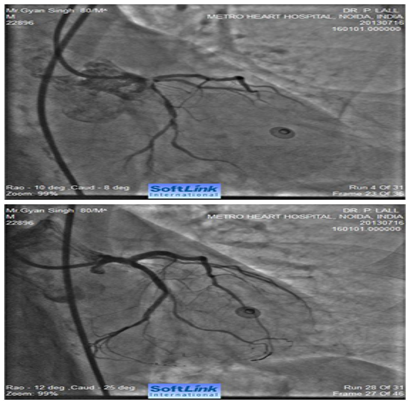

Figure 2 A 60 years old male with recent anterior wall MI and LV ejection fraction of 0.35 with Class III exertional angina. Cranially angulated LAO view shows 95% stenosis of ostial left main coronary artery (LMCA). The ostial LMCA lesion was pulverized with a 1.5 mm RA burr (Boston Scientific International S.A., France) over a 0.009” RotaWire (Boston Scientific International S.A., France). Corresponding image on the right side shows fully opened-up LMCA.